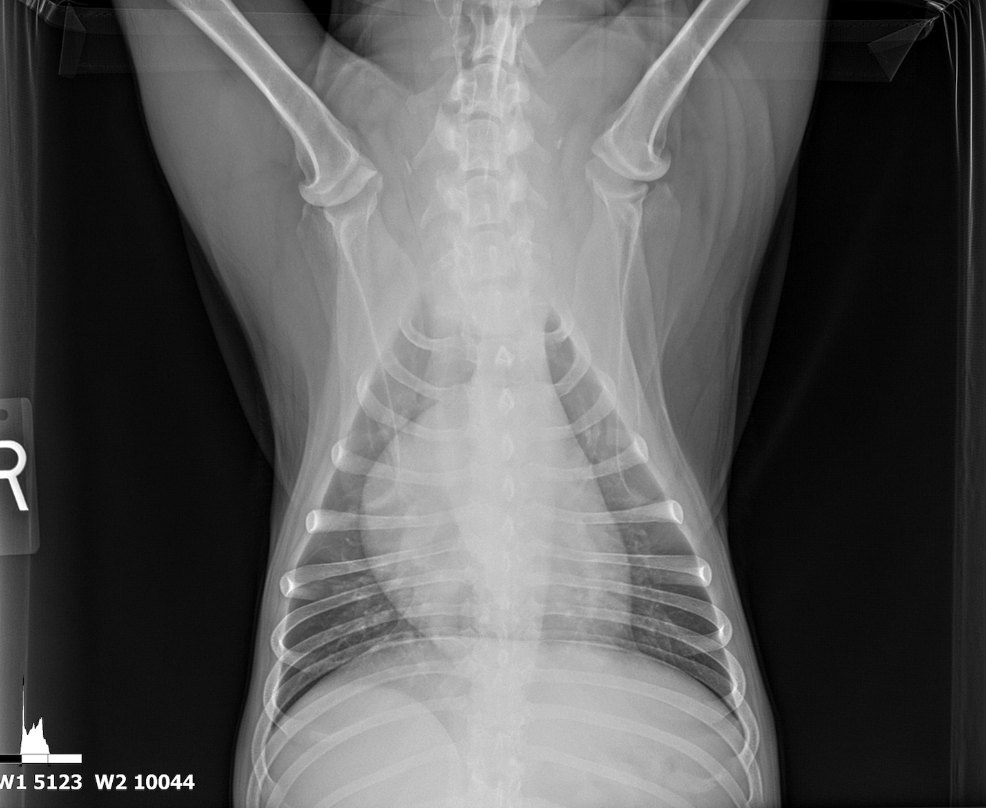

The patient was referred from another veterinary clinic for advanced imaging following the identification of a suspected abdominal mass on radiographs. Ultrasonographic evaluation revealed a splenic mass consistent with an abscess, from which purulent fluid was aspirated and drained. A splenectomy was scheduled for later the same day.

The spleen revealed an expansive parenchymal mass that measured 10+ cm without evidence of cavitation. Hyperechoic fat was noted around the spleen. This is consistent with inflammation.

- Splenic mass.

There was no obvious evidence of metastatic disease. Proactive splenectomy, liver inspection and biopsy was indicated. Rapid echocardiogram was recommended if not already performed to ensure that metastatic disease was not present. Differentials included benign hyperplasia, hemangiosarcoma and round cell neoplasia. However, the mass was highly precarious and at risk for rupture.